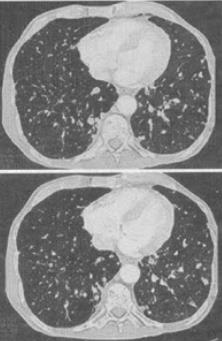

- 单项选择题 患者女,56岁,乳腺癌手术后,未行化疗,结合CT图像,最可能的诊断是()。

A、肺转移瘤

B、肺结核

C、间质性肺炎

D、肺结节病

E、肺曲菌病

- A